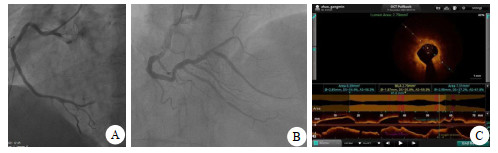

病例2,女,61岁。持续性心前区疼痛52 h,加重15 h,心电图提示:前壁、下壁ST-T改变(图 5)。cTnI 19.25 ng/mL,CK-MB 98.2 ng/mL(图 6),以非ST段抬高型心肌梗塞收住。评估后急诊PCI示罪犯血管OM 100%(图 7A),打通后置入2.25 mm×31.00 mm支架,PDA起始部95%狭窄(图 7B),FFR 0.78,LAD中段狭窄70%(图 7C),FFR 0.84(阴性),于PDA放置2.75 mm×29.00 mm支架,OCT测定支架远端膨胀不全,近端贴壁不良(图 8A),分别后扩球囊反复扩张,OCT再次检查无膨胀不全及贴壁不良现象(图 8B),FFR 0.92(图 8C),心肌酶趋势如图 6所示。

| A为PDA支架远端膨胀不全,近端贴壁不良;B为反复球囊后扩后膨胀不全及贴壁不良消失;C为后扩支架后PDA-FFR 0.92 图 8 病例2的PCI前后FFR及OCT检查结果 |

OCT虽然冠脉造影是诊断冠心病常用有效的方法,但它只是一个二维平面图像,无法了解血管内的情况,存在一定的局限性。OCT的问世极大地弥补了冠脉造影的不足[8],可以识别包括正常血管、脂质斑块、纤维斑块、钙化斑块、易损斑块、血栓、夹层和内膜撕裂,以及其他血管内病理影像。OCT是目前分辨率最高的腔内影像学技术[9],可以探查生物组织内部的微观结构,又被称为“光学活检”。OCT能给出精准的支架尺寸、粗细、长度,并能确定放在何处更合适。病例2的右冠后降支安放支架后OCT检查发现支架远端膨胀不全,近端贴壁不良,经反复球囊后扩直至OCT检查所放支架无贴壁不良及膨胀不全。因此认为AMI的抢救使用OCT可更及时地发现与处理急诊PCI。支架膨胀不全和贴壁不良是PCI术后再狭窄、形成血栓致使长期效果不好的主要原因[10],引起严重钙化和纤维化的冠脉病变。尽管采用切割球囊等措施,但仍无法克服这些弊端,而ROTA技术则能消除这种缺点,使支架术后的长期效果增加[5]。对于AMI非罪犯血管且有严重钙化者择期旋磨后再放支架,长期效果会更好。病例1的PL 100%,为罪犯血管,先开通罪犯血管PL,球囊扩张后置入支架。PDA 75%,LAD 80%是非罪犯血管,PDA FFR 0.76,置入2.5 mm×31.0 mm支架后FFR 0.88造影显示狭窄消失,LAD经OCT检查冠脉内严重环状钙化,如同期勉强PCI,容易引起冠脉夹层甚至破裂的不必要麻烦,改择期ROTA后再放支架,既安全又可靠。